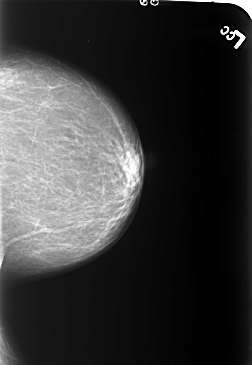

B_3233_1.RIGHT_MLO

RIGHT_MLO LINES 5600 PIXELS_PER_LINE 3888 BITS_PER_PIXEL 12 RESOLUTION 50 OVERLAY

FILE: B_3233_1.RIGHT_MLO.OVERLAY

TOTAL_ABNORMALITIES 4

ABNORMALITY 1

LESION_TYPE MASS SHAPE OVAL-LYMPH_NODE MARGINS CIRCUMSCRIBED

ASSESSMENT 2

SUBTLETY 4

PATHOLOGY BENIGN_WITHOUT_CALLBACK

ABNORMALITY 2

LESION_TYPE CALCIFICATION TYPE COARSE DISTRIBUTION N/A

ABNORMALITY 3

ABNORMALITY 4